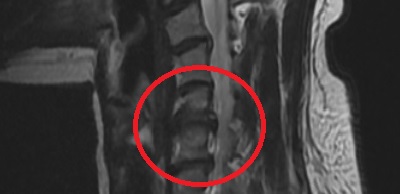

협착증

@ 제가 목디스크 탈출 또는 협착증 문제로 2014년도 와 2021년도에 C-PEN을 받았습니다.

그리고 2021년도에는 3살도 안된 조카가 달려오다가 조카 머리와 제 턱이 부딪히면서 하루하루 지나갈 때마다 통증이 점점 심해졌습니다. 진단명은 디스크파열 2주 동안 너무 아프게 시달리다가 결국 시술하게 되었는데 C-PEN과 C-disq(고주파)를 하게 되었습니다. 목이라서 수면 없이 해야 한다는 게 단점이 있긴 한데 병원마다 다른 듯합니다.